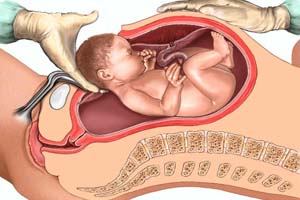

Best Maternity Hospital in Gandhi Path West, Jaipur

Delivering Hope, Health & Happiness

Dr. Himantika Kumawat

MBBS, MS DNB(OBS & GYNAE)